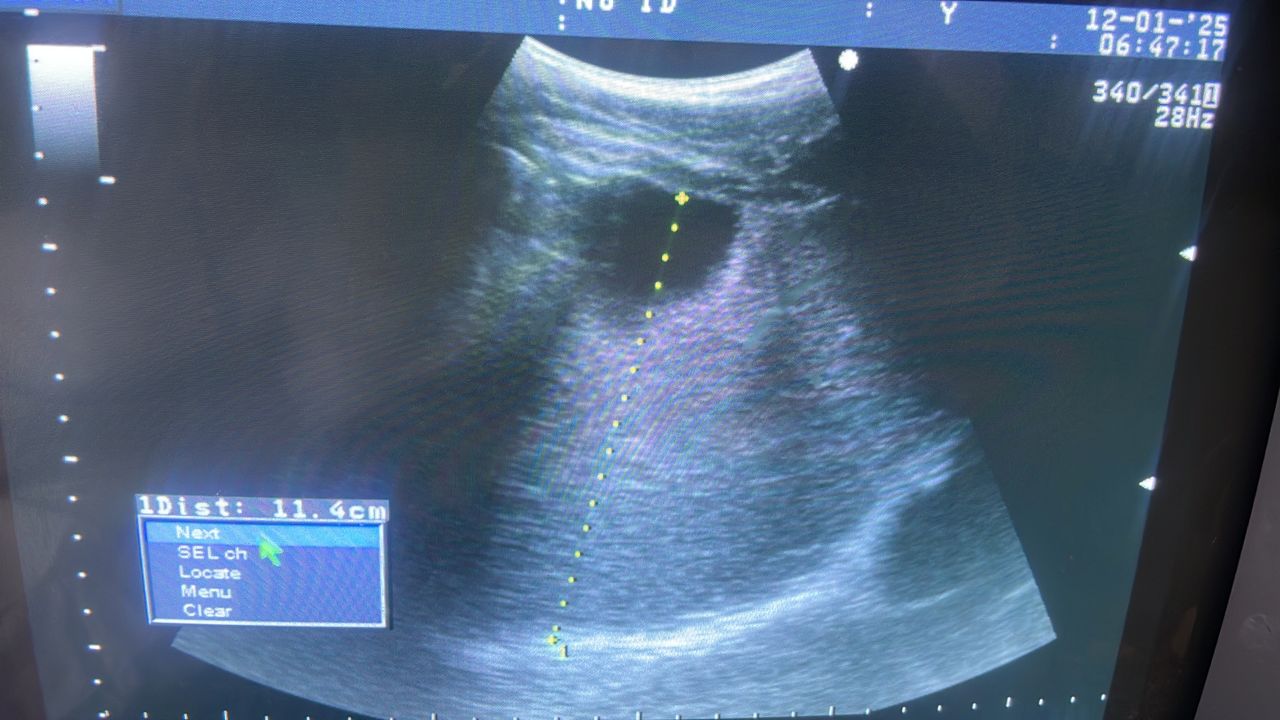

HEPATITIS

Image for HEPATITIS